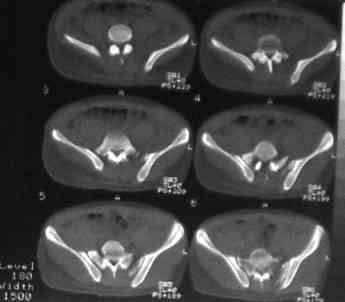

Уважаемые коллеги! На днях оперировал перелом таза месячной давности - разрыв симфиза, перелом обеих ветвей правой лонной кости, трансфораминальный перелом крестца слева. Представляю рентгенограммы с задержкой - технические причины.

Предоперационные рентген и КТ, в операционной - снимки после каждого фиксатора. Вертикальное смещение полностью устранить не удалось. В первую очередь за счет заднего полукольца. Хотя при компрессии на стержнях горизонтальное смещение было сантиметра 1,5. Т.е. крестец, на мой взгляд еще не сросся. От коллег хотел-бы услышать допустима-ли такая остаточная деформация?